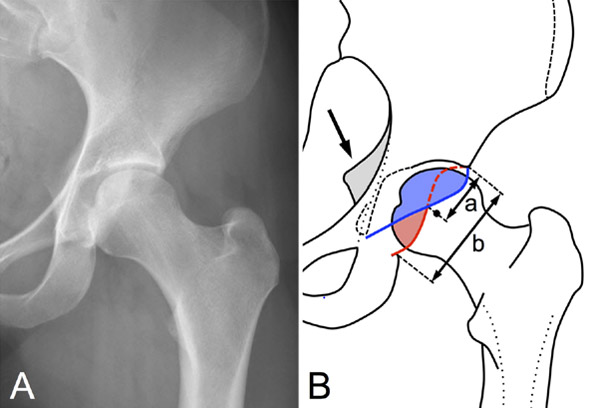

Standard - X-rays

Standard – x-rays

• ✔️ Femoro acetabular impingement Pincer type By TRUE acetabular retroversion (acetabular posterior dysplasia)

3 signs: cross-over sign, ischial spine sign, posterior wall sign

Retroversion index > 30%

Femoro acetabular impingement Pincer type By TRUE acetabular retroversion